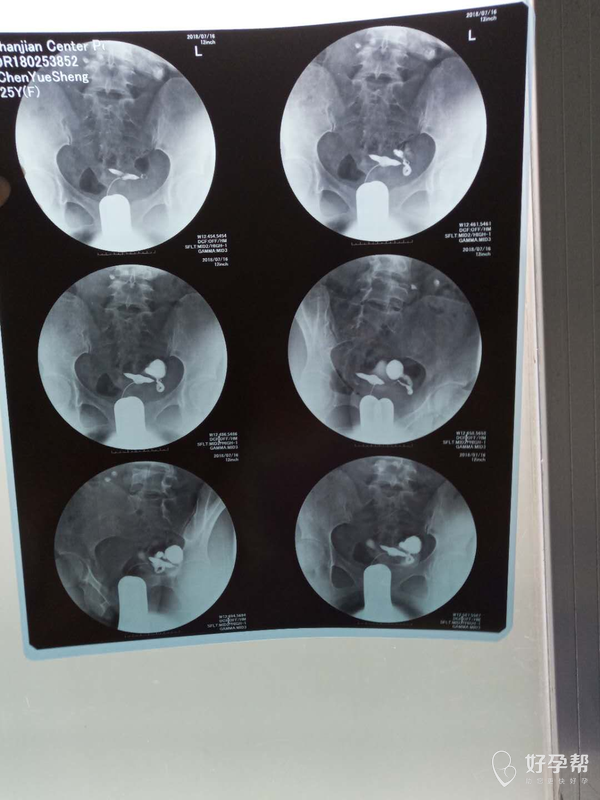

这种必须做手术么还是取了胚胎不是非要做

这个手术不是非得要马上做,需要根据你的年龄、生育计划等来综合评估并权衡利弊后再决定是否需要手术以及什么时候做。如果是做试管通常为了避免输卵管积液及炎症因子逆流至宫腔影响胚胎着床等,会行输卵管结扎等手术,这个手术通常在移植前完成